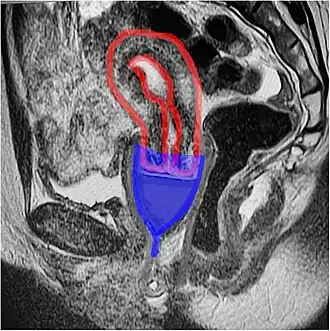

Cross-sectional diagram showing the uterus, cervix, fornix on either side of the cervix, vagina, and pubic bone. Ring-shaped cups lie in the upper portion of the vagina, with the inner edge in the posterior fornix and outer one held in behind the pubic bone, within the pelvic floor.

Because bell-shaped cups are commonly depicted as being placed in the vaginal canal, well below the cervix, they are also called "vaginal cups", with the ring-shaped cups called "cervical cups". This may not clearly reflect their position in the body. MRI imaging suggests that, contrary to some manufacturer's depictions, the bell-shaped cups called "vaginal cups" are placed over the cervix, in a position similar to a cervical cap (not to be confused with a cervical cup).[7] Ring-shaped cups, called "cervical cups", also cover the cervix, but have one edge next to the cervix, and the other located further down the vagina, so that the cup is nearly parallel to the long axis of the vagina.[24]

Many drawings show bell-shaped cups located far down the vagina, but this contradicts in-vivo imaging.[7]

While many diagrams show bell-shaped menstrual cups very low in the vagina, with the vagina gaping open, in-vivo imaging shows that the cups sit high, with their rim around the cervix, and the vagina squishes shut below the cup, sealing it inside the body.[7]